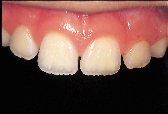

| Figure 2: Post-operative view of the restored fractured distal incisal edge of the right central incisor done without any mechanical tooth preparation. |

Consider, for example, the common occurrence of a fractured incisal edge in a newly erupted central incisor of a child patient. Traditionally, the perimeter of the fractured tooth substance is chamfered to accommodate an increase in the bondable substrate area and to allow for an imperceptible tooth restoration. In many instances, the preparatory procedure removes more sound tooth structure than the initial trauma. This irreversible tooth preparation will affect all future restorative interventions. In the case of the eight-year-old patient depicted in Fig. 2, restoration of the distal incisal edge of the right central incisor was done without the use of any mechanical tooth preparation. The slightly compromised esthetic result (shown 18 months after a second traumatic episode fractured the adjacent lateral incisor) was counterbalanced by the fact that the restoration was done without further loss of sound tooth substance. The restoration should last approximately five years, at which point an improved restorative material will allow for an enhanced esthetic result. This case is illustrative of an evolving restorative mentality that acknowledges: